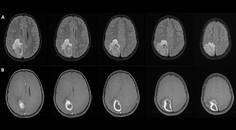

Focal Status Epilepticus 9 Years After Brain Abscess